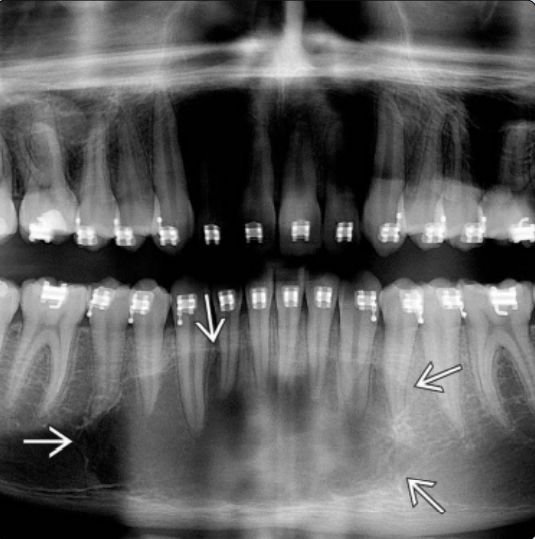

1β. Οδοντοφόρος Κύστη

Οι οδοντοφόρες κύστεις είναι οι δεύτερες σε συχνότητα εμφάνισης οδοντογενείς κύστεις, και αποτελούν τις πιο κοινές αναπτυξιακές κύστεις των γνάθων.

Εξ ορισμού η οδοντοφόρος κύστη προσφύεται στον αυχένα και περιβάλλει τη μύλη ενός εγκλείστου δοντιού.

Οι οδοντοφόρες κύστεις απαντώνται συχνότερα σε σχέση με τρίτους γομφίους της κάτω ή άνω γνάθου και κυνόδοντες της άνω γνάθου, οι οποίοι είναι και οι συχνότεροι τύποι έγκλειστων δοντιών.

Η υψηλότερη επίπτωση των οδοντοφόρων κύστεων εμφανίζεται κατά τη δεύτερη και τρίτη δεκαετία της ζωής και έχουν υψηλότερη επίπτωση στους άντρες.

Συνήθως τα συμπτώματα απουσιάζουν, ενώ η καθυστερημένη ανατολή ενός δοντιού είναι η συχνότερη ένδειξη ύπαρξης οδοντοφόρου κύστης. Οι ασθενείς είναι δυνατό να παρατηρήσουν αργά αυξανόμενη διόγκωση. Μια κύστη μπορούσε να φτάσει τα 4-5 εκ. σε διάμετρο σε χρονικό διάστημα 3-4 ετών. Η κύστη είναι δυνατό να φτάσει σε μεγάλες διαστάσεις, ενώ σπάνια φτάνει σε τέτοιο μέγεθος ώστε να προδιαθέτει σε παθολογικό κάταγμα. Σε περίπτωση επιμόλυνσης, η κύστη μπορεί να γίνει επώδυνη.

Μπορεί να παρατηρηθεί ακόμη απορρόφηση των ριζών των παρακείμενων δοντιών, που έχουν ήδη ανατείλει. Φαίνεται μάλιστα πως οι οδοντοφόρες κύστεις εμφανίζουν μεγαλύτερο δυναμικό απορρόφησης παρακείμενων ριζών σε σχέση με άλλα είδη κύστεων, κάτι που αποδίδεται στον ιδιαίτερο ρόλο του οδοντοθυλακίου.

Η αφαίρεση των εμπλεκόμενων δοντιών και η εκπυρήνιση των μαλακών μορίων αποτελεί οριστική θεραπεία στις περισσότερες των περιπτώσεων. Όταν οι κύστεις επεκτείνονται σε μεγάλο τμήμα της κάτω γνάθου, μια αποδεκτή θεραπευτική προσέγγιση είναι η μαρσιποποίηση ή στοματοποίηση της κύστης, ώστε να επιτραπεί η αποσυμπίεση και η επακόλουθη σμίκρυνση της βλάβης, μειώνοντας έτσι την έκταση της επέμβασης για εκτομή της βλάβης, που ενδεχομένως να χρειασθεί να γίνει σε δεύτερη φάση.